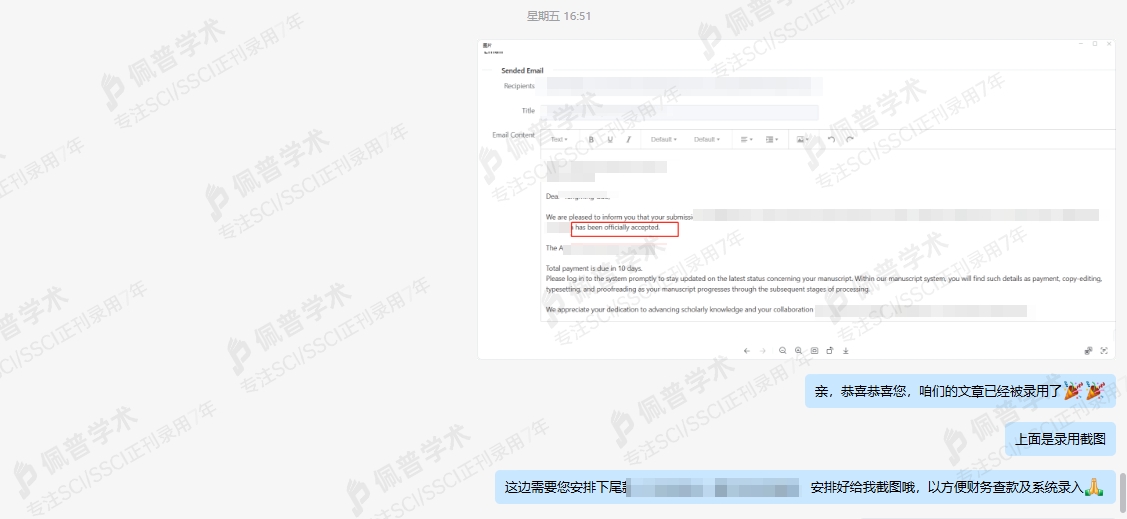

接收函展示